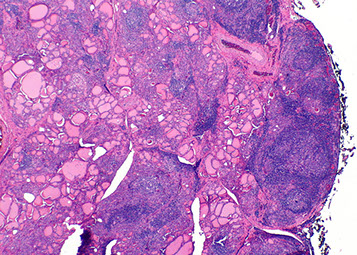

minimally invasive follicular ca

Lymphovascular invasion - minimally invasive follicular ca

Follicular Carcinoma

2nd MCC thyroid ca (10-20%)

2 types of tumors: widely invasive and minimally invasive

- minimally invasive tumors indistinguishable from follicular adenoma grossly, except that the capsules of follicular carcinoma are thicker and more irregular

- widely invasive follicular ca can have extensive permeation of capsule grossly

Micro:  uniform follicules c colloid (like normal thyroid); cannot differentiate a follicular carcinoma from a follicular adenoma based purely on cytology, but need to see an invasive component (in or through capsule or vascular invasion) or distant mets

- look out for vascular invasion (in our outside of capsule) that is attached to the BV wall

-- tumors plugging the BV may become endothelialized

- nuclei lack features of papillary ca, and psammoma bodies are not present